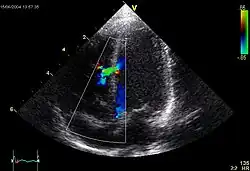

Mitralstenose

Klinik: Leistungsminderung durch die diastolische Füllungsstörung mit Reduktion des Herzzeitvolumens (HZV), Belastungsdyspnoe, spät: Facies mitralis („rote Bäckchen“), periphere Zyanose, Zeichen der Rechtsherzinsuffizienz, Tachyarrhythmia absoluta bei Vorhofflimmern.

Kompl.: Vorhofdilatation mit Vorhofflimmern und evtl. Vorhofthrombose und Embolie, Rückstau in die Lunge (Lungenstauung, Lungenödem) und ggf. bis in den großen Kreislauf (pulmonale Hypertonie, Rechtsherzbelastung/Cor pulmonale, Rechtsherzinsuffizienz), bakterielle Endokarditis.

![]() |